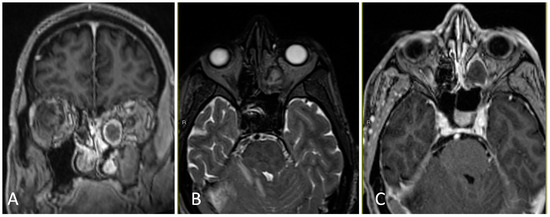

3.3.2. Illustrative Case